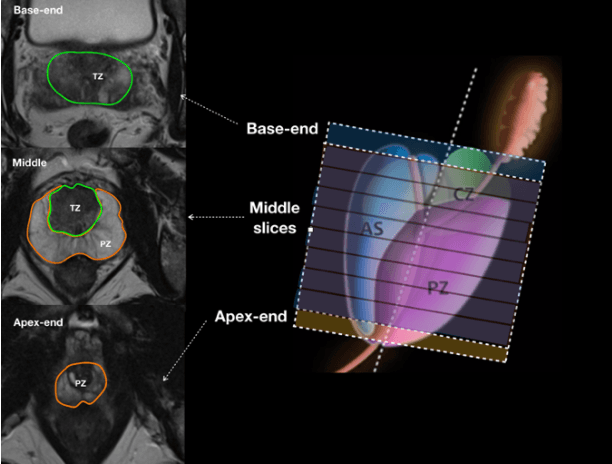

Abstract:Prostate cancer is the second leading cause of cancer death among men in the United States. The diagnosis of prostate MRI often relies on the accurate prostate zonal segmentation. However, state-of-the-art automatic segmentation methods often fail to produce well-contained volumetric segmentation of the prostate zones since certain slices of prostate MRI, such as base and apex slices, are harder to segment than other slices. This difficulty can be overcome by accounting for the cross-slice relationship of adjacent slices, but current methods do not fully learn and exploit such relationships. In this paper, we propose a novel cross-slice attention mechanism, which we use in a Transformer module to systematically learn the cross-slice relationship at different scales. The module can be utilized in any existing learning-based segmentation framework with skip connections. Experiments show that our cross-slice attention is able to capture the cross-slice information in prostate zonal segmentation and improve the performance of current state-of-the-art methods. Our method significantly improves segmentation accuracy in the peripheral zone, such that the segmentation results are consistent across all the prostate slices (apex, mid-gland, and base).

Abstract:Our main objective is to develop a novel deep learning-based algorithm for automatic segmentation of prostate zone and to evaluate the proposed algorithm on an additional independent testing data in comparison with inter-reader consistency between two experts. With IRB approval and HIPAA compliance, we designed a novel convolutional neural network (CNN) for automatic segmentation of the prostatic transition zone (TZ) and peripheral zone (PZ) on T2-weighted (T2w) MRI. The total study cohort included 359 patients from two sources; 313 from a deidentified publicly available dataset (SPIE-AAPM-NCI PROSTATEX challenge) and 46 from a large U.S. tertiary referral center with 3T MRI (external testing dataset (ETD)). The TZ and PZ contours were manually annotated by research fellows, supervised by genitourinary (GU) radiologists. The model was developed using 250 patients and tested internally using the remaining 63 patients from the PROSTATEX (internal testing dataset (ITD)) and tested again (n=46) externally using the ETD. The Dice Similarity Coefficient (DSC) was used to evaluate the segmentation performance. DSCs for PZ and TZ were 0.74 and 0.86 in the ITD respectively. In the ETD, DSCs for PZ and TZ were 0.74 and 0.792, respectively. The inter-reader consistency (Expert 2 vs. Expert 1) were 0.71 (PZ) and 0.75 (TZ). This novel DL algorithm enabled automatic segmentation of PZ and TZ with high accuracy on both ITD and ETD without a performance difference for PZ and less than 10% TZ difference. In the ETD, the proposed method can be comparable to experts in the segmentation of prostate zones.